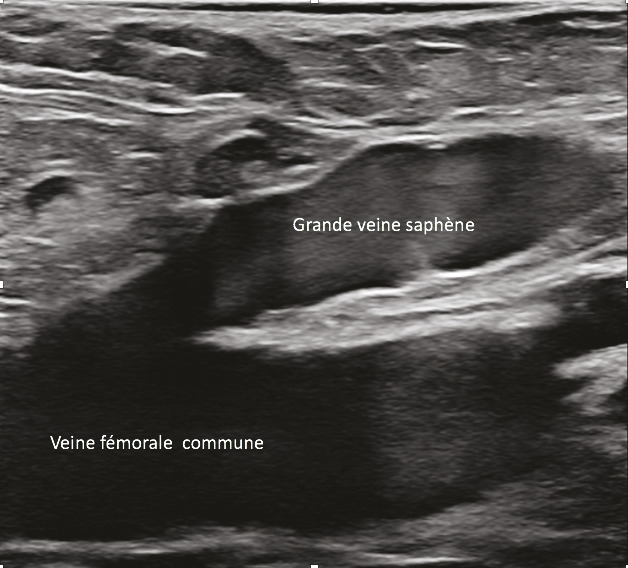

L’échographie en mode B, qui fournit une simple imagerie tissulaire, est utilisée pour identifier le réseau veineux superficiel, analyser les trajets veineux, mesurer le diamètre des veines pathologiques et analyser leur paroi et leur système valvulaire (fig. 12 et 13).